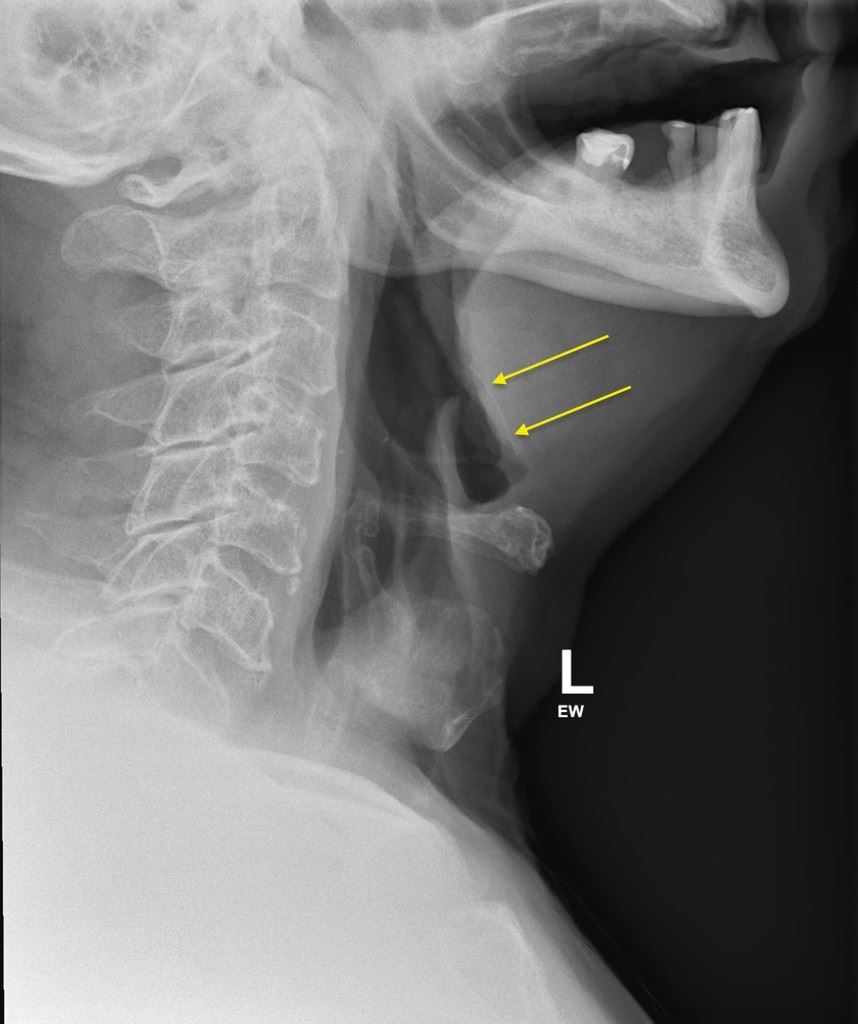

Malangnya, semasa memakan hidangan pedas itu, dia merasakan sesuatu pada lehernya, yang ternyata adalah sekeping tulang ayam kecil.

Walau bagaimanapun, apabila rasa itu berterusan, dia akur dan akhirnua pergi berjumpa doktor. Doktor kemudian mengesahkan bahawa ada tulang ayam kecil tersekat pada lehernya, tetapi meyakinkannya bahawa itu bukanlah masalah yang serius.

Namun satu kejutan baginya apabila pakar Telinga, Hidung, dan Tekak (ENT) mencadangkan agar dia minum empat tin air bergas untuk mencairkan tulang tersebut. Dia mendapati ubat tersebut satu rawatan yang unik, tetapi memutuskan untuk mencubanya. Dia kemudian membeli empat tin air bergas dari pasaraya dan terkejut apabila dia berasa lebih baik pada keesokan paginya. Pada hari berikutnya, dia sudah kembali seperti biasa.